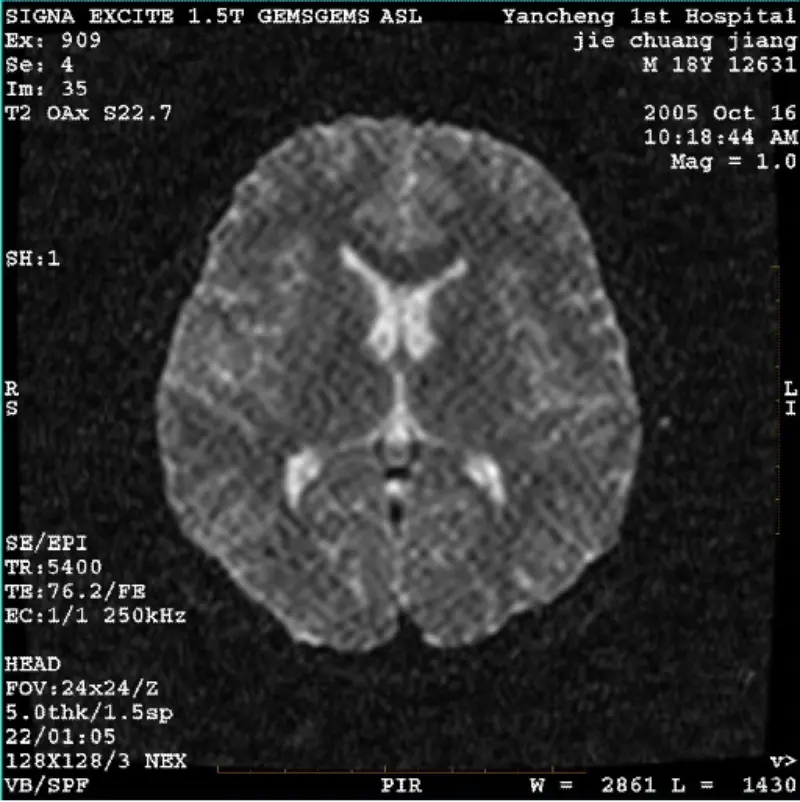

СИСТЕМ: 1.5Т Сигна Твин Екците ИИ (верзија софтвера 11.0М4) ПРОБЛЕМ/СИМПТО ДВИ (режим зумирања и цео режим) и фиеста (режим зумирања и цео режим) има слику видљиви мрежасти или сумотни артефакт, без обзира када користите намотај за тело или главу калем, друга рутинска слика изгледа нормално